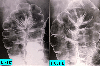

Multiple Lymphomatous Polyposis type malignant lymphoma of the large intestine followed up for several times.

Malignant Lymphoma/MLP type